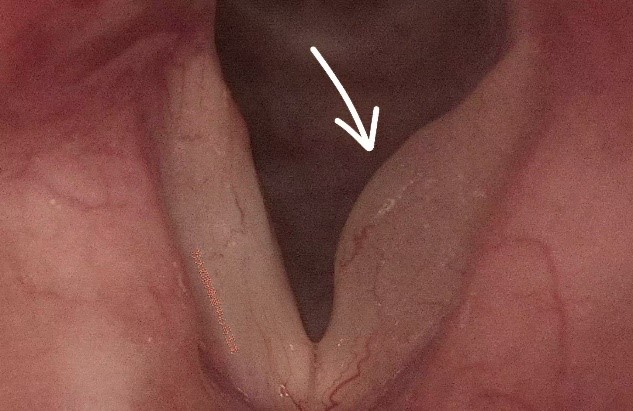

刘女士平时在上海工作生活,近2年来声音嘶哑逐渐加重,在外院就诊后诊断为“声带任克水肿”,专家建议手术。因为声带部位手术的特殊性,刘女士思考后决定审慎对待,要经过多方专家诊断结果一致后再做决定。在家人的推荐下,刘女士来到苏州大学附属第四医院嗓音专病门诊进一步就诊。在嗓音专病门诊,马玉龙副主任医师为刘女士做了动态频闪喉镜检查,发现左侧声带任克间隙水肿比较明显,严重影响声带黏膜波,导致声音嘶哑,发音费力。综合评估后建议声带显微外科手术治疗。